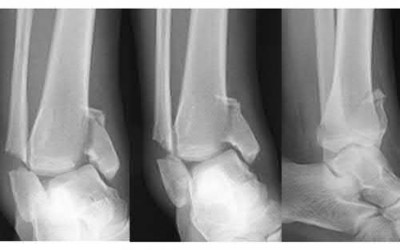

Figures and Illustrations:

Figures A through C are AP, oblique, and lateral radiographic views of a right ankle demonstrating displaced fractures of the lateral and posterior malleoli. Figure D is an axial CT scan of the right ankle following closed reduction and splint application.